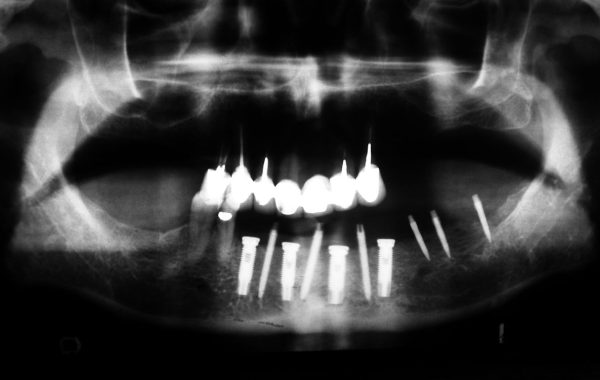

Paciente #6

Aquí tenemos otro caso de una paciente de 65 años de edad a la cual se le colocaron 12 implantes. Seis de ellos en el maxilar para soportar una dentadura sin paladar y los otros seis en las partes posteriores de la mandíbula para colocarle prótesis fijas cementadas.

Radiografía con los 12 implantes colocados